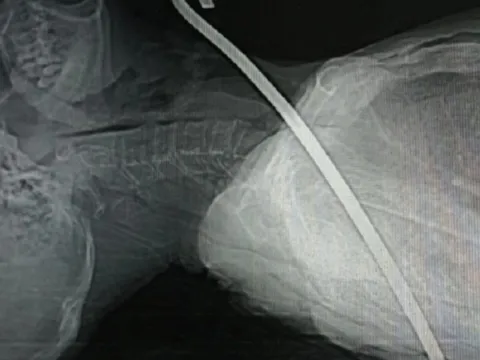

Vấp ngã bị thanh xà beng dài cả mét đâm xuyên cổ

Người bệnh vào viện trong tình trạng tỉnh táo, thanh xà beng dài ghim ở cổ. Bệnh nhân được các bác sĩ tiến hành cầm máu, nhanh chóng sơ cứu, siêu âm mạch...